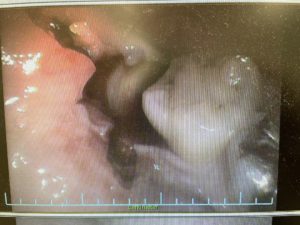

ほら、微妙に頭をひょっこりとだしているでしょう、これが親知らずです。まずはctをとって神経との位置を確認、ほっぺた側ベロ側をしっかりと確認していきます。ほっぺた側にある場合の方が当然ながらぬきやすいです。

いやーだいぶ内側はいってますねー

とりあえず歯茎を切開して、全貌をみていきます。当然視野の確保というのはとても重要ですからね。

ほらみえてきた。根っこの部分がみえてきたので、ここからは、分割作業にはいっていきます。

これが、前方の頭だけおとした画像の状態です。あとは、根っこの部分をだすだけです。これで動けばおっけー。動かなかったら、さらに根っこを分割(根分割と言います)していくのですが、ぬけました。

ほら、なくなっているでしょう?